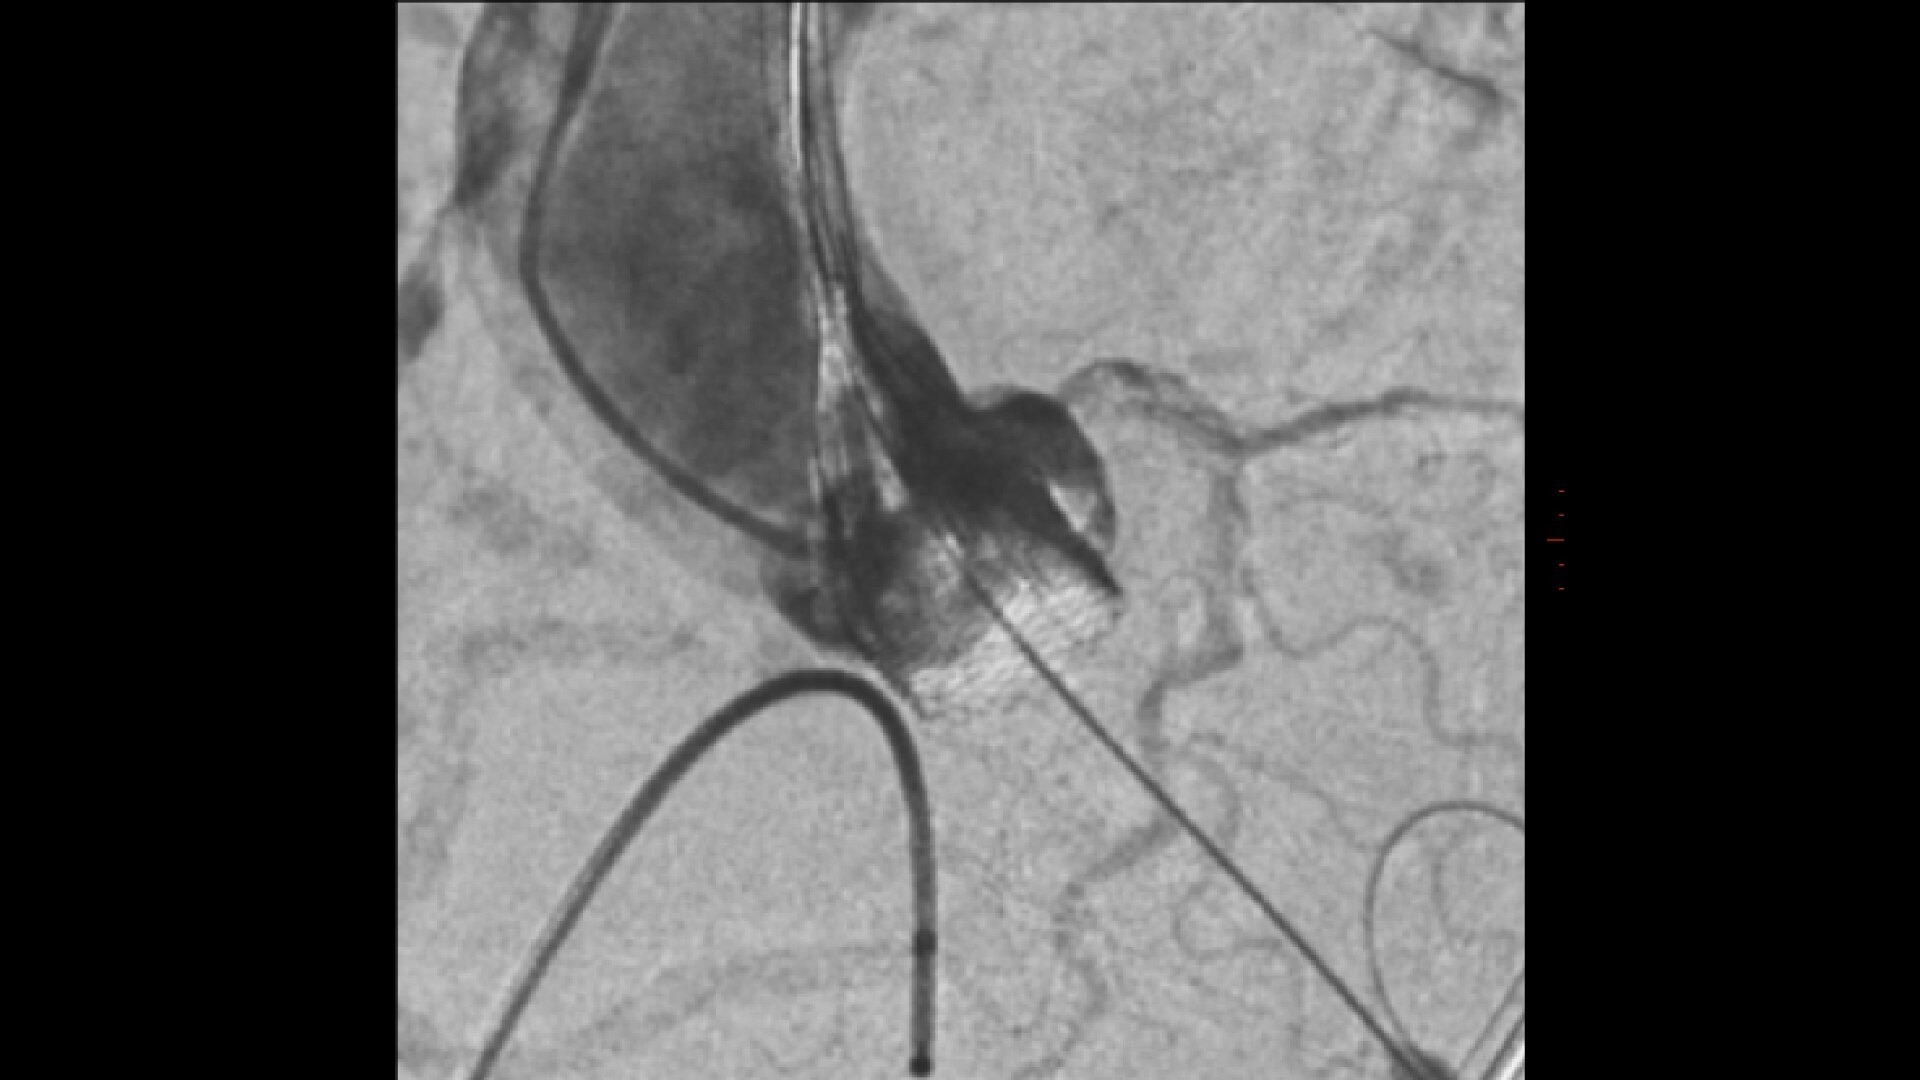

Transcatheter aortic valve implantation

Streamlined workflow for your TAVI procedures

GUIDE

3D fusion guidance enhanced with Calcification Enhancement improves the visualization of moving contrasted structures.